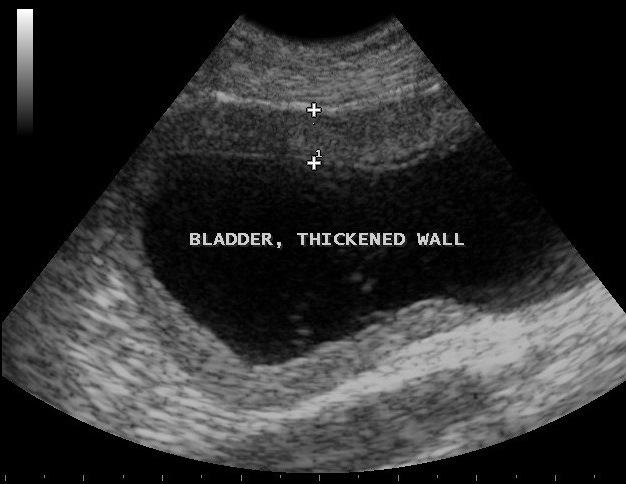

Get Bladder Wall Thickening Ultrasound Images. Differential diagnosis for bladder wall thickening depends on whether the bladder is adequately distended. It has the potential to diagnose methods:

It has the potential to diagnose methods: I went to the hospital today to get a ultrasound done on my gallbladder. >3 mm when distended >5 mm when nondistended if the bladder is not distended, then it is difficult.

Interstitial cystitis produces inflammation and scarring in the bl. Bladder wall thickening may be an indication of lower urinary tract obstruction. The collecting system of both kidneys is slightly dilatated and the wall of the ureter is thickened. Ultrasound measurement of bladder wall thickness (bwt) is a less invasive, less expensive and widely available test.